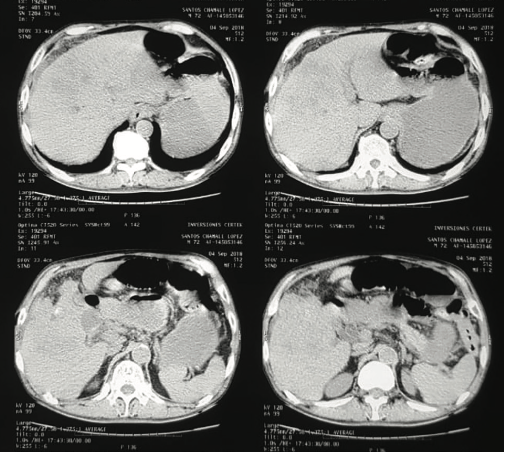

Durante la evaluación diagnóstica se presenta un cuadro de obstrucción intestinal con resolución espontanea, de- bido a que puede haber migración del lito intraluminal re- solviendo momentáneamente el cuadro obstructivo. En estudios de imágenes podemos mencionar inicialmente

hallazgos en rayos x que presenta neumobilia, dilatación de asas intestinales e imagen de un lito intraluminal (tria- da de Simon). En tomografía estos hallazgos son visualiza- dos con mayor calidad de imagen2,4.

Laboratorios de ingreso con leucocitosis (13,500) y for- mula diferencial con neutrofilia (92%), química sanguínea sin alteración hidroelectrolítica, con bilirrubinas totales en 2.1 directa en 1.6 indirecta en 0.5, GGT en 560. A las 6 horas de ingreso distensión mejora y logra defecar por lo que continua en observación. A las 12 horas del ingreso paciente vuelve a distenderse y presentar vómitos por lo que se realiza tac abdominal (Figuras 2 y 3).

Figura 2. Tomografía abdominal que demuestra a nivel hepático neumo- bilia, además no se logra diferenciar adecuadamente lecho vesicular ni vía biliar, únicamente imágenes de infiltración a nivel de lecho hepático.